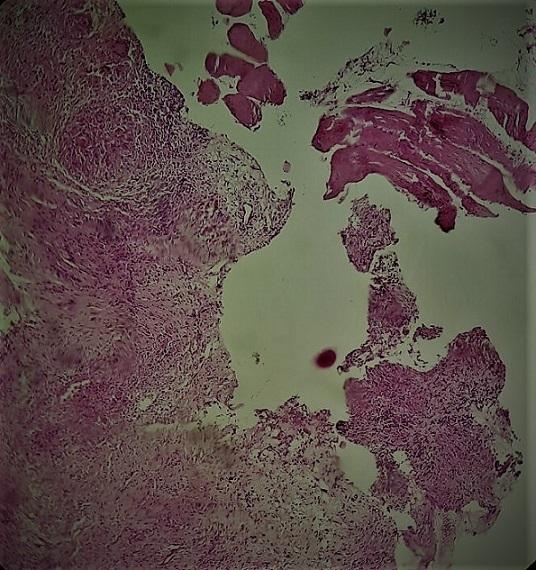

Soft tissue tuberculosis is one of the rare forms of extrapulmonary tuberculosis. Furthermore, isolated muscular tuberculosis is exceptional. We here report the original case of a young immunocompetent patient with isolated muscular tuberculosis involving major pectoralis muscle. The diagnosis was mainly based on histology. The patient was successfully treated with anti bacterial therapy only. This rare case study has been combined with a literature review.

摘要

软组织结核是肺外结核的罕见形式之一。此外,孤立性肌肉结核更是罕见。我们在此报告一例原本健康的年轻患者发生累及胸大肌的孤立性肌肉结核的病例。诊断主要基于组织学检查。该患者仅通过抗菌治疗即获成功治愈。本罕见病例报告还结合了文献综述。